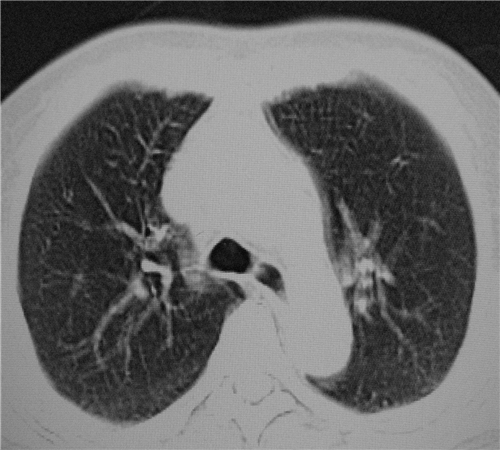

标题: CT26849:女67岁反复胸痛两天余,临床考虑夹层。 [打印本页]

标题: CT26849:女67岁反复胸痛两天余,临床考虑夹层。

右肺感染,未见夹层。

1)右肺感染性病变。2)建议行ct增强扫描或mri检查排除主动脉夹层。

双下肺感染,右侧显著。有无夹层,增强扫描后再诊断。

1.考虑双肺感染,右侧为重;2.建议ct增强或mri排除主动脉夹层

双下肺感染,右侧显著。有无夹层,增强扫描后再诊断。食道未见异常。